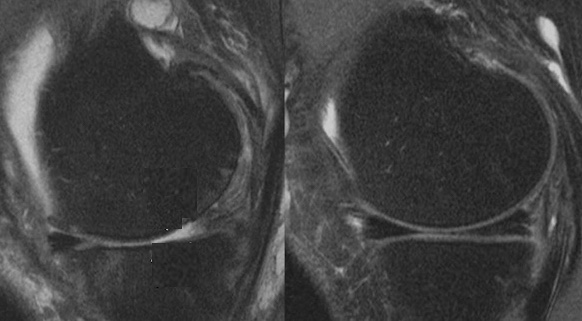

Une étude publiée dans le Journal of Medical Imaging & Radiation Sciences (JMIRS) se propose de déterminer si les images acquises avec un appareil 0,3 T sont diagnostiquement comparables à celles acquises avec un appareil 1,5 T et d'évaluer l'impact des éventuelles différences sur la visibilité des structures anatomiques, le RSB, le rapport signal/bruit et la durée de l'examen. Ce travail a été mené auprès de 25 volontaires sains. L'imagerie a été réalisée à l'aide d'un système IRM Esaote O-Scan Light 0,3T et d'un système GE Optima 450 W 1,5T.

L'imagerie DP FSE a été effectuée dans les plans sagittal, transversal et coronal. Les images acquises ont été évaluées par une analyse subjective, par trois radiologues, et objective, à l'aide du logiciel ImageJ, qui a permis de mesurer le RSB et le rapport contraste/bruit (CNR). Les chercheurs ont trouvé une qualité d'image (RSB et CNR) avec des différences statistiquement significatives au niveau du ménisque médial dans le plan coronal et du cartilage articulaire dans le plan transversal. Aucune différence statistiquement significative n'a été observée dans les mesures du fémur distal sur le plan sagittal.

L'analyse subjective des images a, d’autre part, révélé des différences significatives en faveur de l'IRM 1,5T pour tous les critères observés au niveau des ligaments croisés, des ménisques latéral et médial, du cartilage articulaire et quant à la qualité globale de l'image. Sans surprise, c’est l'IRM à champ magnétique plus élevé (1,5T) qui a permis d'obtenir de meilleurs résultats que celle à champ magnétique plus faible (0,3T). Toutefois, il convient de noter que les valeurs d'évaluation subjective, comprises entre 2,7 et 4,0, indiquent une visualisation de bonne à excellente qualité de l'anatomie étudiée.